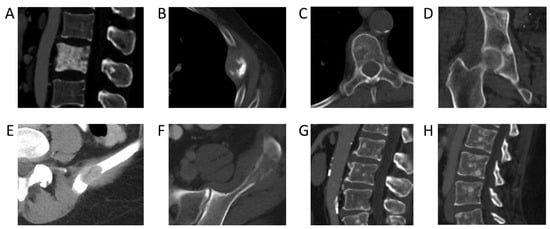

Incidence rates of bone metastases across colorectal, ovarian, genitourinary, and gastric cancers were low (from 10–20%). The lowest incidence rates were found in central nervous system cancer, with an incident rate of 8% (95% CI: 4–11%) and testicular cancer, with an incident rate of 5% (95% CI: 4–6%). Examples of CT images from cancers with a low incidence rate of bone metastases are shown in Figure 3. Prior studies based on autopsy data report higher incidences of bone metastases in breast (67% vs. 41%), prostate (66 vs. 52%), and lung cancer (36 vs. 33%) [8]. This discrepancy can possibly be explained by the fact that patients in our study were evaluated at earlier time points in their cancer journey, whereas autopsy studies are evaluated only once patients have succumbed to their cancer. On the other hand, autopsy studies have reported lower incidences of bone metastases than our NLP-derived results for colorectal cancer (11% vs. 16%) [9,10] and ovarian cancer (9% vs. 11%) [9]. This may be partially attributable to advances in treatment options and associated increased survival, with more patients today living long enough to develop bone metastases. For example, with the introduction of adjuvant treatment regimens, the median survival of patients with advanced colorectal cancer has increased to more than 20 months, with a corresponding increase in the likelihood of developing bone metastases and having adverse skeletal-related events [9,10,11,12,13,14]. The utilization of NLP to extract information from routine CT staging scans affords us the ability to better evaluate the temporal development of bone metastases during a patient’s cancer journey.

Figure 3. Bone metastases from primary cancers with the highest incidence rates. (A) Sclerotic pelvic metastases in a 76-year-old male patient with prostate cancer. (B) Left 5th rib lytic metastasis in an 84-year-old male with colorectal cancer. (C) Lytic metastasis T5 vertebra in a 64-year-old female patient with ovarian cancer. (D) Sclerotic metastasis right acetabulum in a 62-year-old male patient with urothelial cancer. (E) Lytic metastasis left ilium in a 54-year-old female patient with renal cell cancer. (F) Lytic metastasis left ilium in a 44-year-old male patient with renal cell carcinoma. (G) Multiple sclerotic lumbar spine metastases in a 54-year-old male patient with urothelial carcinoma of the renal pelvis. (H) Sagittal CT lumbar spine of multifocal sclerotic osseous metastases in a 35-year-old female patient with HER2-negative gastric cancer.